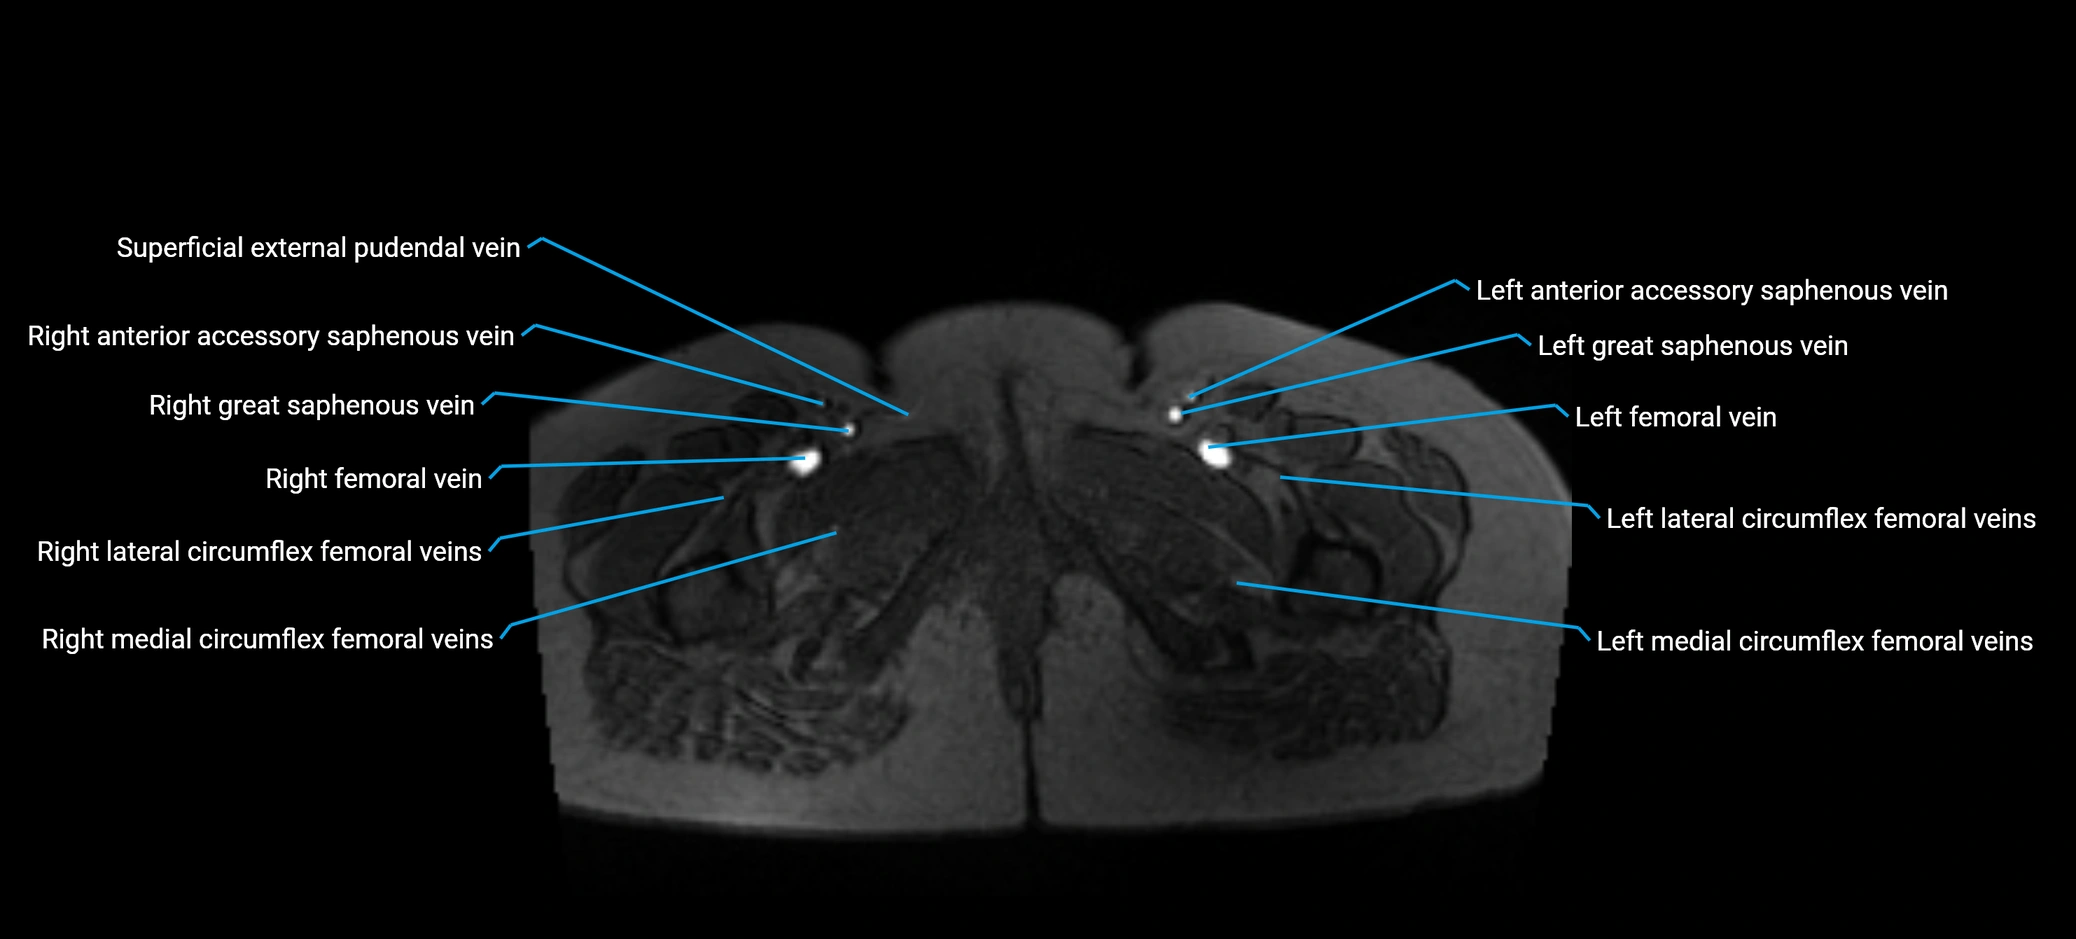

MRI image

image